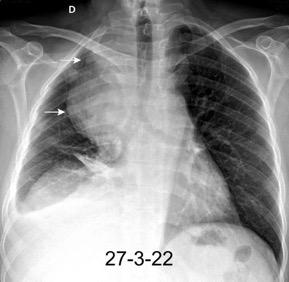

Marzo 2014: Perforación longitudinal distal secundaria a episodio de vómito (síndrome de Boerhaave). Derrame pleural izdo. que evoluciona a empiema.

Wang C-T et al. Tension hydropneumothorax in a Boerhaave syndrome patient: A case report . World J Emerg Med, 2021. Katabathina V et al. Nonvascular, nontraumatic mediastinal emergencies in adults:a comprehensive review of imaging findings. Radiographics. 2011.